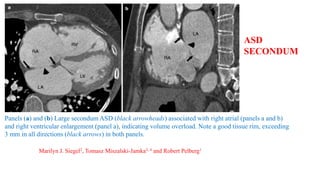

Panels (a) and (b) Large secondum ASD (black arrowheads) associated with right atrial (panels a and b)

and right ventricular enlargement (panel a), indicating volume overload. Note a good tissue rim, exceeding

3 mm in all directions (black arrows) in both panels.

Marilyn J. Siegel2, Tomasz Miszalski-Jamka3, 4 and Robert Pelberg1

ASD

SECONDUM